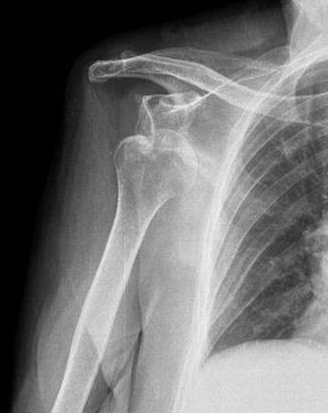

OMUZ ÇIKIĞI

Doktor Mehmet Subaşı

Omuz vücudumuzun en esnek eklemidir. Top fırlatmak, sırtımızı kaşım...